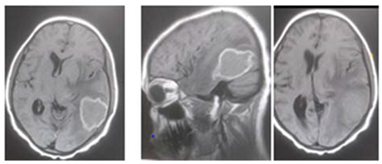

This is 18years Sudanese young female, university student, an otherwise healthy before, presented to neurosurgery emergency unit with history of rabidly progressing headache for 6 months duration, few weeks before her appearance she exhibit visual blurring that end in decrease visual acuity in both eyes, she has inability to walk steady.

Neurological examination, revealed conscious patient, with just perception to light and there was increase tone and exaggerated reflexes on both lower limbs.

Operation: Before the decision of surgery, we talked to the patient and her family clearly about the surgery complications and post operative outcome. Through left tempro- parito-occipital craniotomy, the tumor was macroscopically totally resects. It was sub cortical, well circumscribed ill define capsule, extended deeply to the underlining temporal horn of the lateral ventricle .Dural graft was taken from the tempralis fascia and was closed in water tide.

Patient was fully recovered from anesthesia and was taken to the ICU on nasal oxygen mask.

Histopathology

Brain tubeclomata ( extra pulmonary tuberculosis)

Patient was put on anti-tuberculosis according to the international protocol, and discharged free of headache, can see objects.